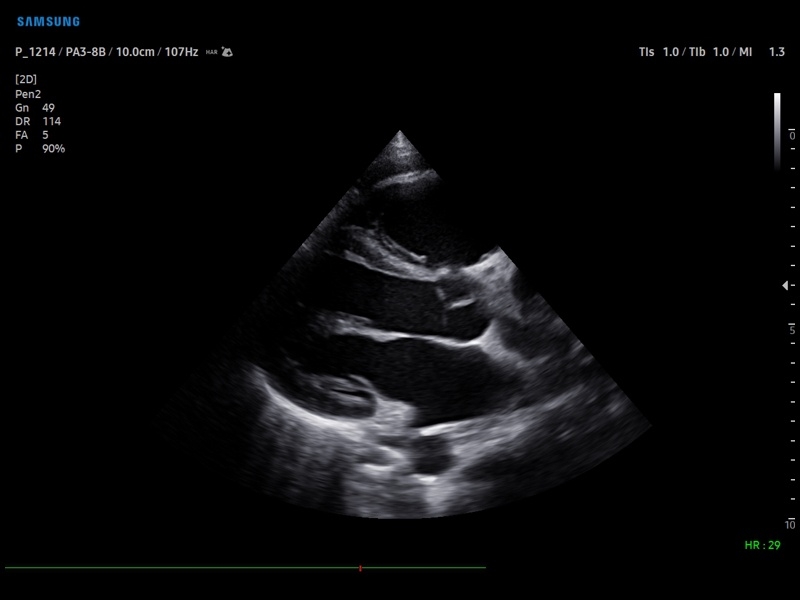

• Кардиология

• M - одномерный режим для исследования сердца, анатомический М-режим (необходим кардиопакет), CM - цветной М-режим (необходим кардиопакет).

• Кардиопакет: тканевый допплер (TDI) + анатомический М-режим + цветной М-режим (CM) + программное обеспечение.

• Пакет кардиологических исследований.

М-режим:измерение диаметра аорты, передне-заднего размера ЛП, толщины МЖП (систолическая и диастолическая), толщины ЗСЛЖ (систолическая и диастолическая), размеров ЛЖ и ПЖ (систолический и диастолический), ФВ (Teichholz).

B-режим:измерение диаметра аорты (восходящей, дуги, нисходящей, на уровне синусов Вальсальвы, на уровне створок аортального клапана), определение размеров ЛП и ПП (максимальный, минимальный, систолический, диастолический, переднее-задний, верхнее-нижний, медиально-латеральный), расчет объемов ЛП и ПП, объемов ЛЖ (метод "Площадь-Длина", метод дисков (Simpson)), массы миокарда ЛЖ, индекса массы миокарда ЛЖ.

CD-режим (ЦДК):измерение радиуса ПФСМР (PISA), полуколичественная оценка трансмитрального, транстрикуспидального, трансаортального и транспульмонального кровотока (оценка регургитации), оценка аномальных сбросов крови через МПП И МЖП.

PW-режим (импульсно-волновой допплер):автоматическая, полуавтоматическая и ручная трассировка допплеровского спектра митрального, аортального и трикуспидального клапанов, клапана легочной артерии, кровотока в выходном тракте ЛЖ и ПЖ (пиковая/средняя скорость, пиковый/средний градиент давления, время изоволюметрического расслабления ЛЖ, время ускорения, замедления, выброса), оценка кровотока легочных и печеночных вен.

CW-режим (постоянно-волновой допплер):программы расчета работы митрального, аортального и трикуспидального клапанов, клапана легочной артерии.

TD-режим (тканевой допплер):количественная оценка локальной сократительной функции стенок ЛЖ и ПЖ.